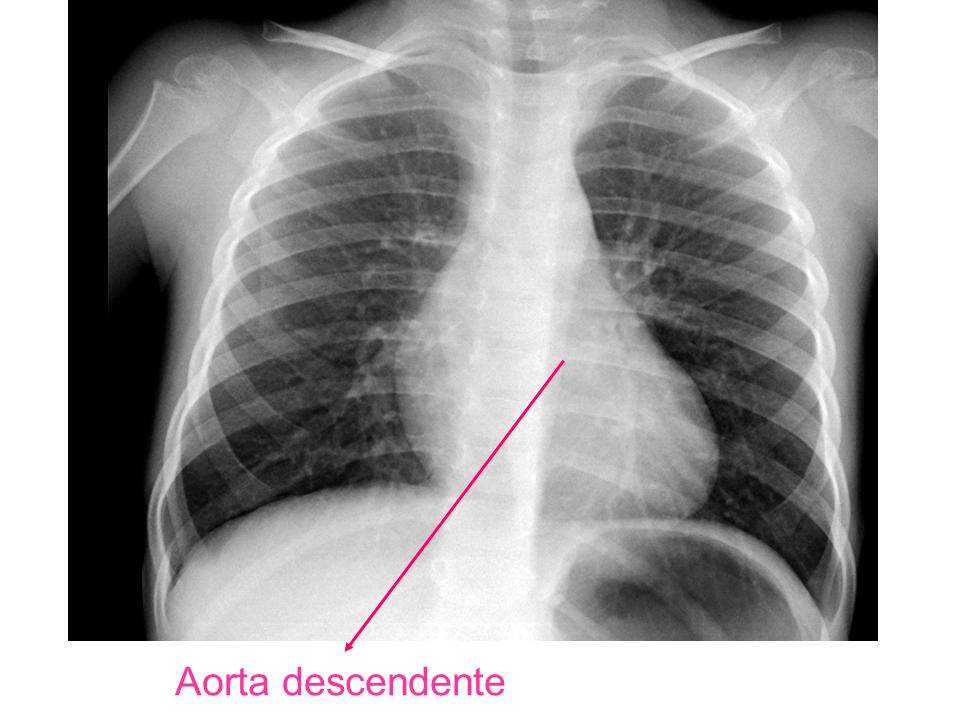

Para una adecuada lectura sistemática de la radiografía de tórax, debemos conocer la anatomía radiológica básica e identificar determinadas estructuras2.

• Aorta descendente